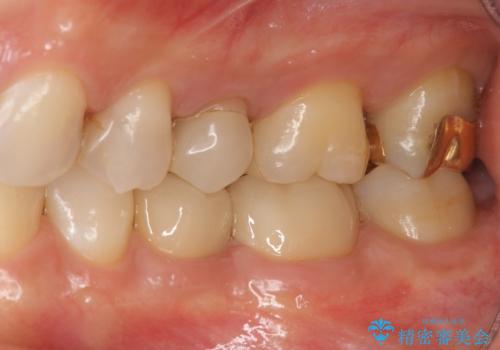

外から見て白くきれいな修復が為されていたとしても、内部で虫歯が再発していることは多々あります。

違和感を感じたら早期にX線検査を行い、神経が保存できるうちに治療を行うことが重要です。